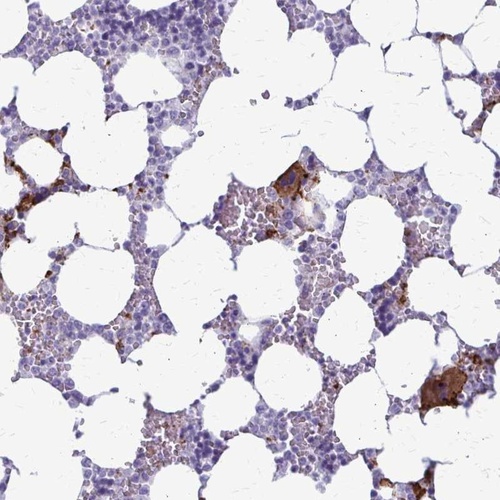

Immunohistochemical staining of human bone marrow shows strong cytoplasmic positivity in megakaryocytes.